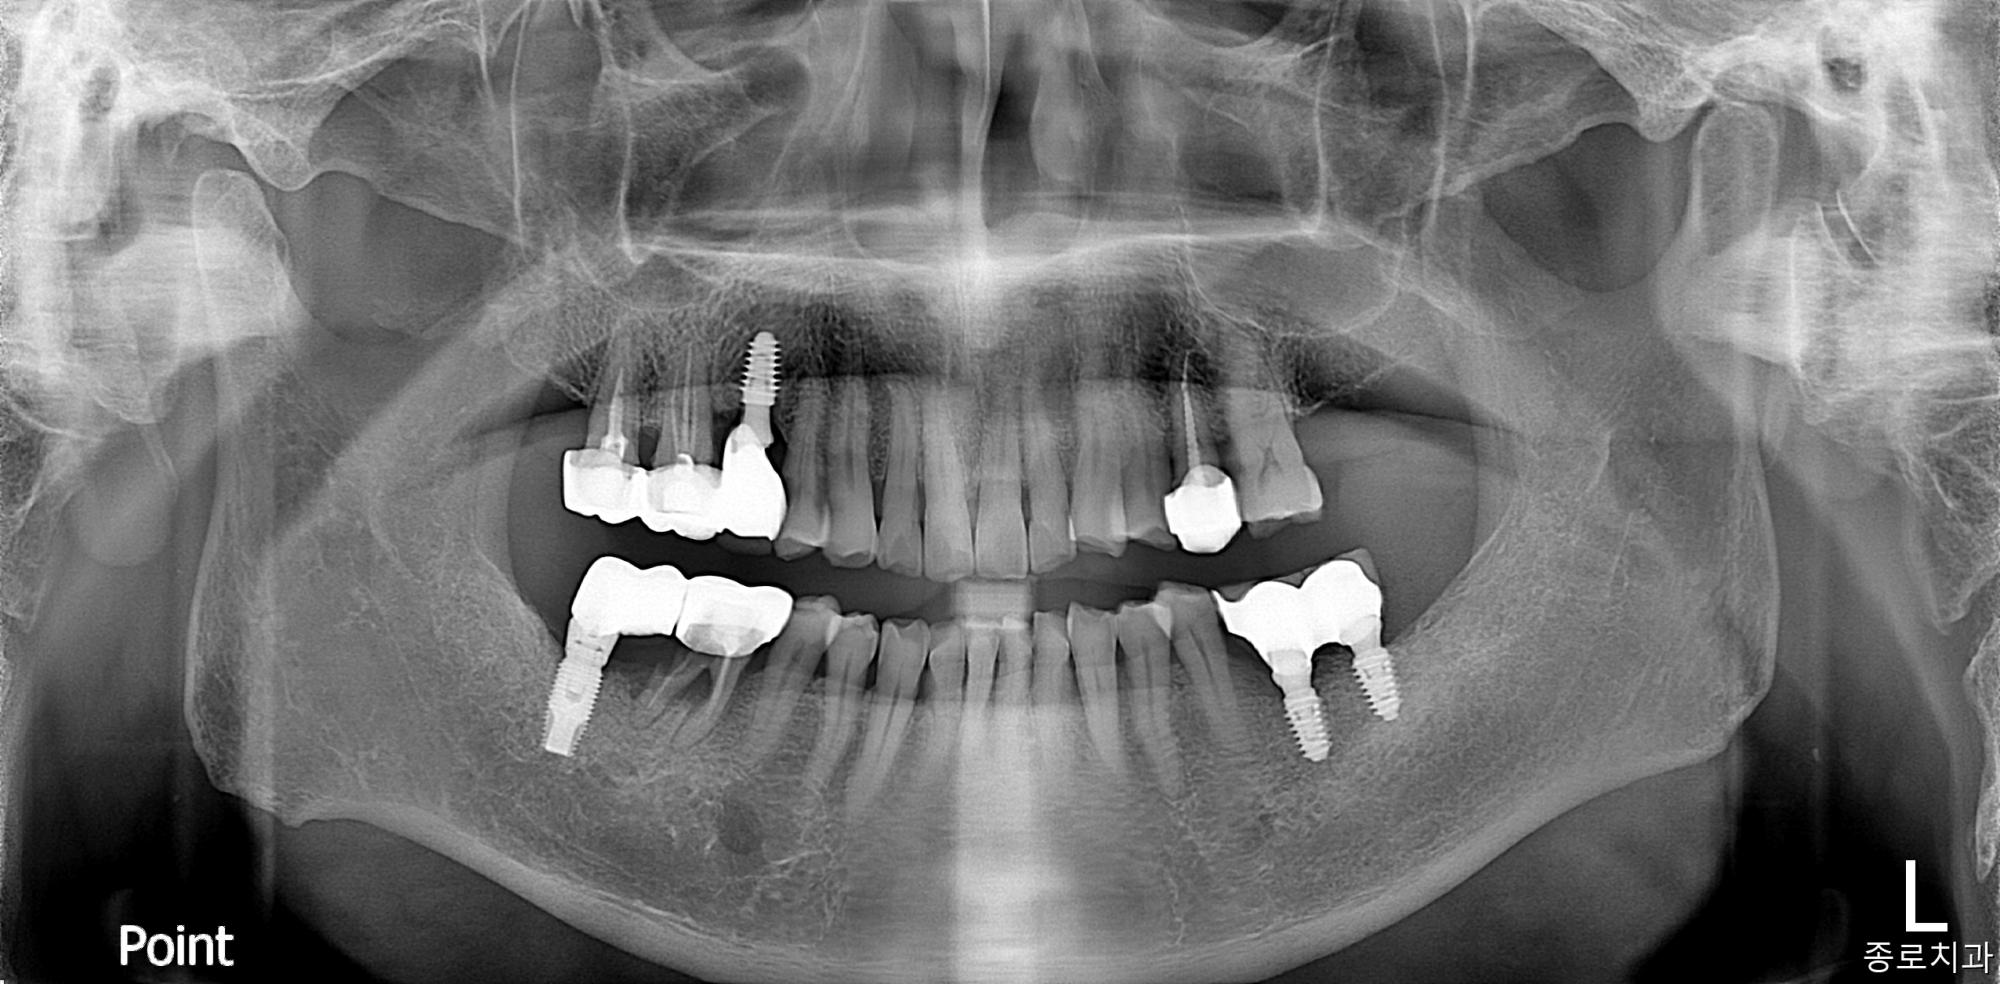

전/후사진

전/후 사진갤러리